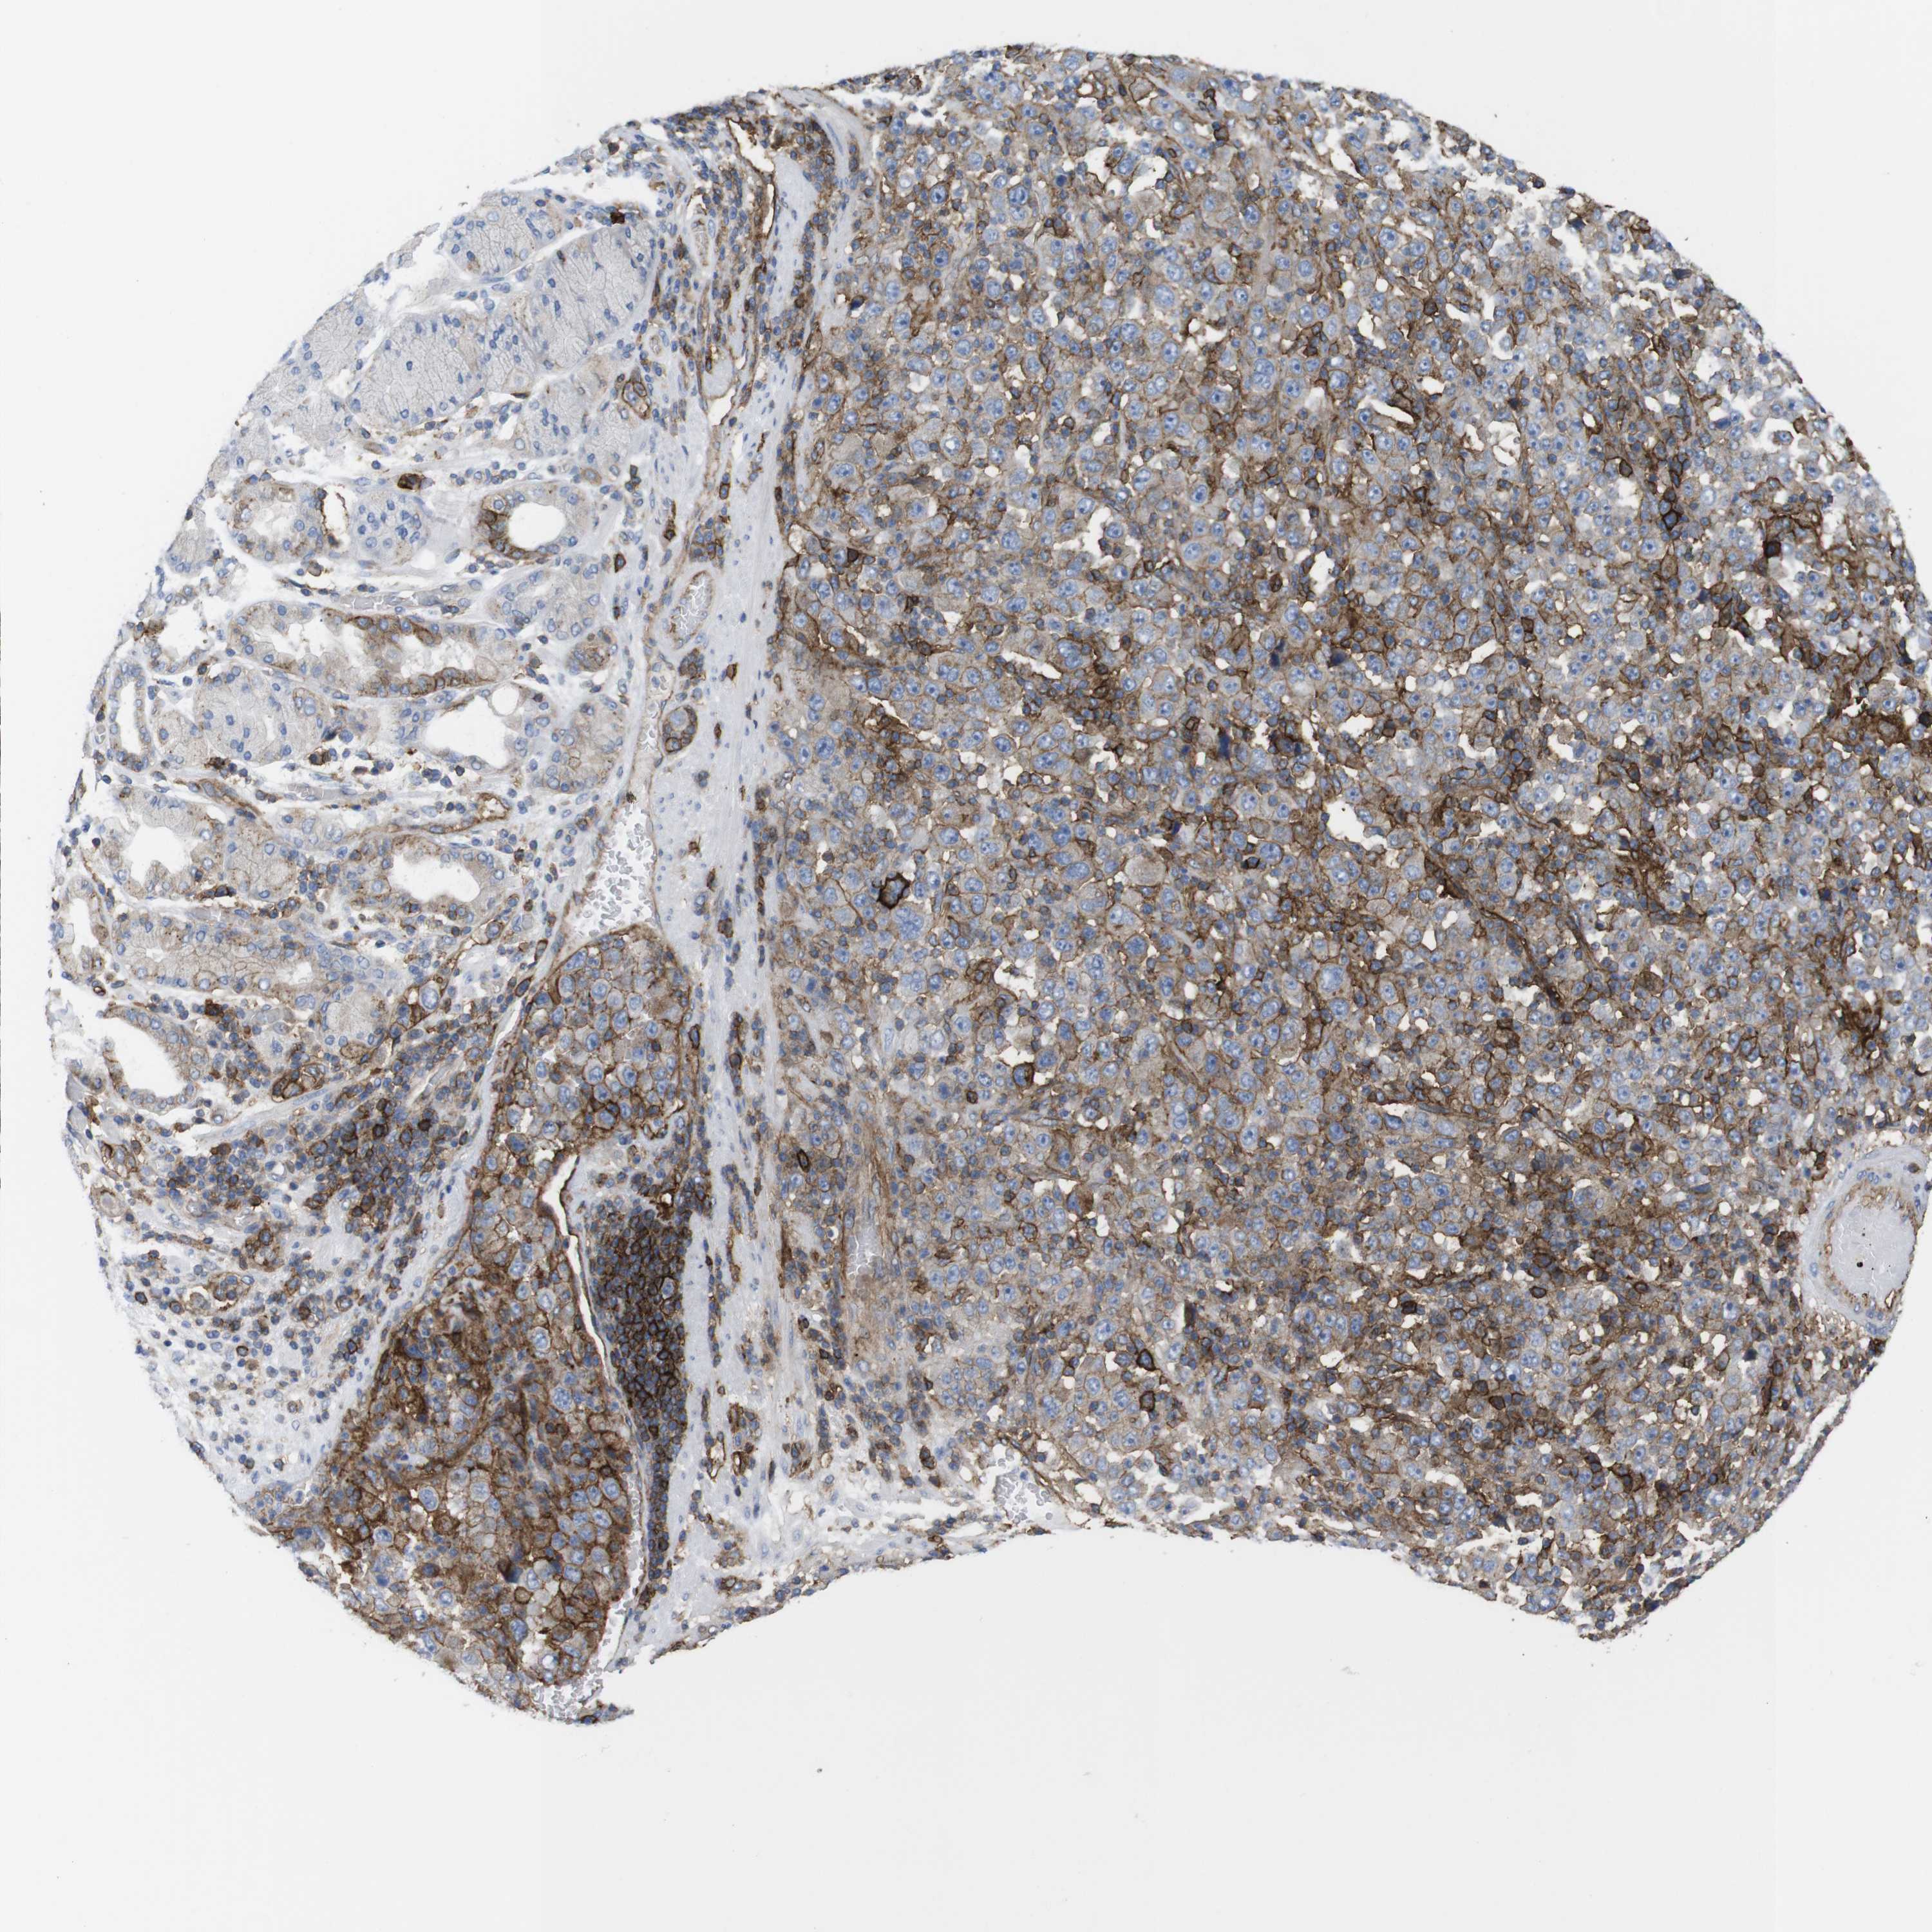

STOMACH CANCER - Protein expressioni

A mouse-over function shows sample information and annotation data. Click on an image to view it in a full screen mode. Samples can be filtered based on level of antibody staining by selecting one or several of the following categories: high, medium, low and not detected. The assay and annotation is described here.

Note that samples used for immunohistochemistry by the Human Protein Atlas do not correspond to samples in the TCGA dataset.

Antibody stainingi

Antibody staining in the annotated cell types in the current human tissue is reported as not detected, low, medium, or high, based on conventional immunohistochemistry profiling in selected tissues. This score is based on the combination of the staining intensity and fraction of stained cells.

Each image is clickable and will lead to virtual microscopy that enables deeper exploration of all samples and also displays staining intensity scores, fraction scores and subcellular localization as well as patient and tissue information for each sample.

Antibody HPA014488

Antibody CAB006820

Staining

High

Medium

Low

Not detected

Intensity

Strong

Moderate

Weak

Negative

Quantity

>75%

75%-25%

<25%

None

Location

Nuclear

Cytoplasmic/membranous

Cytoplasmic/membranous,nuclear

Adenocarcinoma, NOS

Adenocarcinoma, High grade